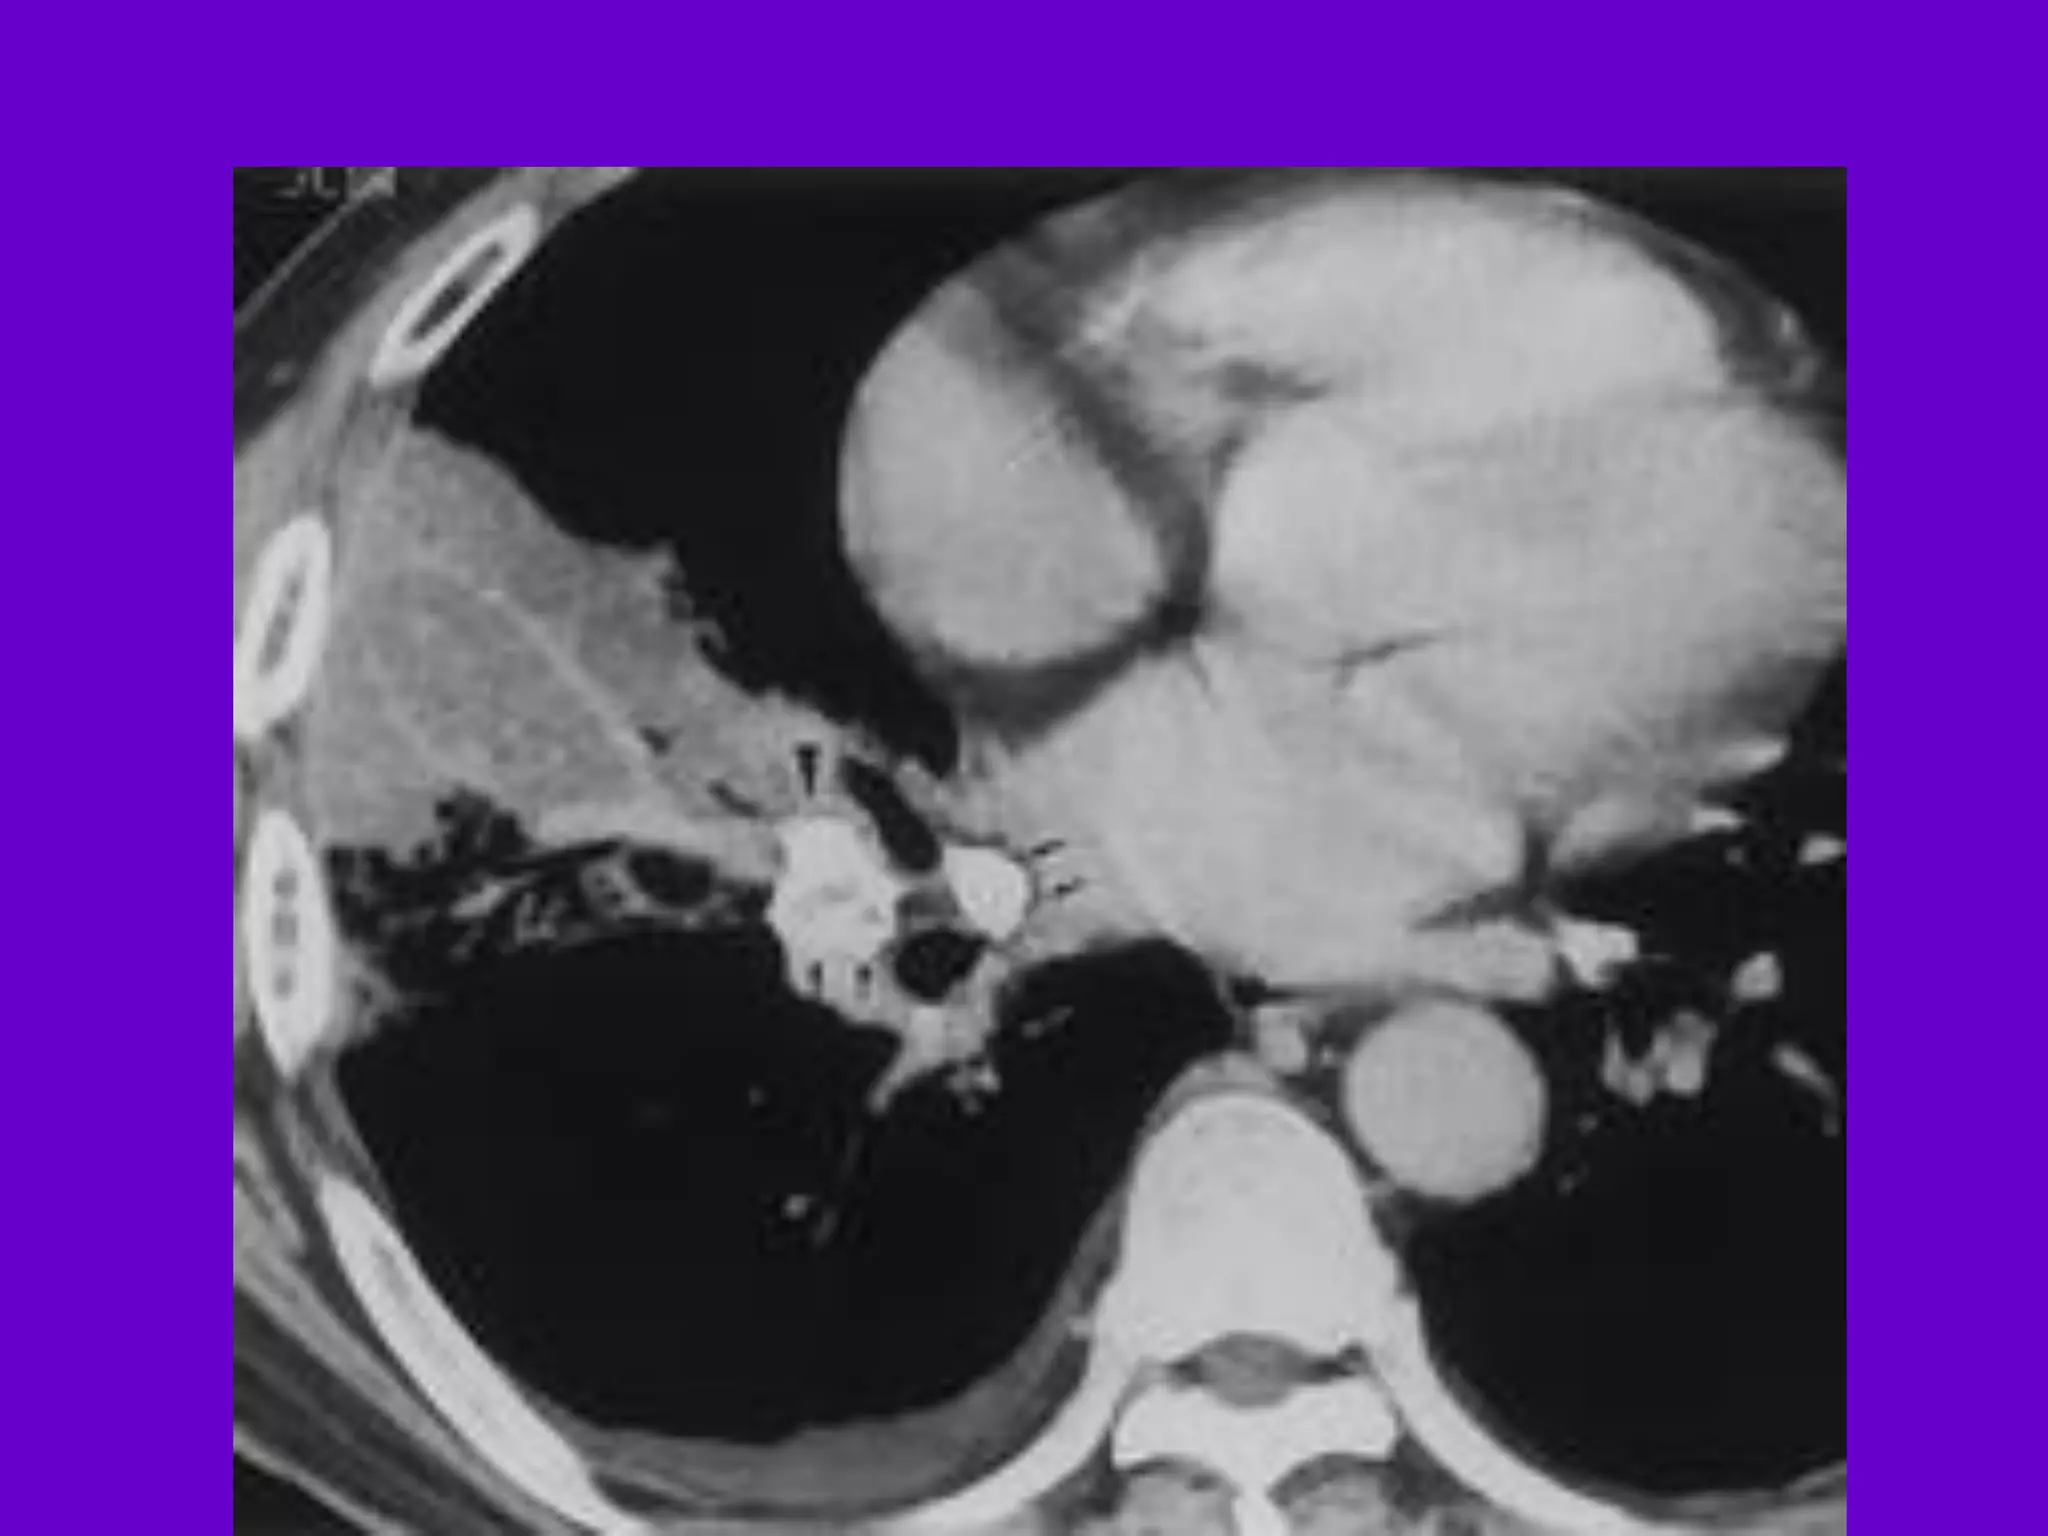

Pulmonary TB :

Lobar Pneumonia

􀂄

CT is superior than plain CXR in picking

up the

consolidation, atelectasis and the hilar LN

thereby

making the diagnosis easy.

􀂄 MRI reveals some of these changes,

however, CT is

the diagnostic modality of choice in such

cases.

Bronchopneumonia

On CT it is usually B/L and widespread,

not always

symmetrical involvement of lungs.

Hilar and Mediastinal

Lymphadenopathy

CT and MRI depict the hilar and

mediastinal LN

equally well.

􀂄 Calcification in the nodes is however

better seen on

CT.

􀂄 Necrosis is seen as focal areas of low

attenuation on

a CECT.

􀂄 On MRI focal necrosis is seen as areas

of increased

signal intensity on T2W images.